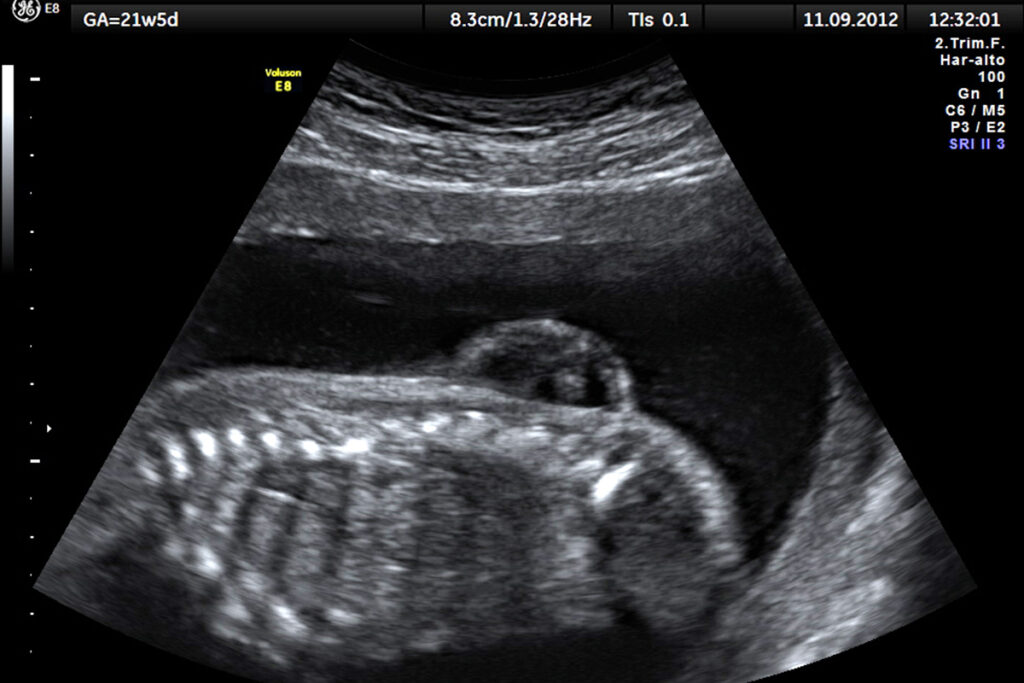

Дочери Ольги Чолак из подмосковного Можайска три года. «На скрининге в перинатальном центре Наро-Фоминска врач сказал: «У вас всё нормально, здоровая девочка»», — рассказывает Ольга. Врач УЗИ не заметил аномалию развития плода, поэтому о диагнозе дочери Ольга узнала только после родов. Увидев новорождённую дочь, врач и акушер были шокированы. «У ребёнка из спины торчит грыжа с грецкий орех, а в [медицинской] карте ничего об этом не написано», — говорит Ольга.

Spina bifida с латыни буквально переводится как «расщепление позвоночника». Это аномалия неизвестного происхождения, которая чаще всего появляется на ранних этапах беременности: при формировании у плода позвоночника некоторые позвонки не закрываются костной тканью, и в результате нервы и оболочки спинного мозга остаются открытыми — как раз из-за этого на спине может появиться грыжа.